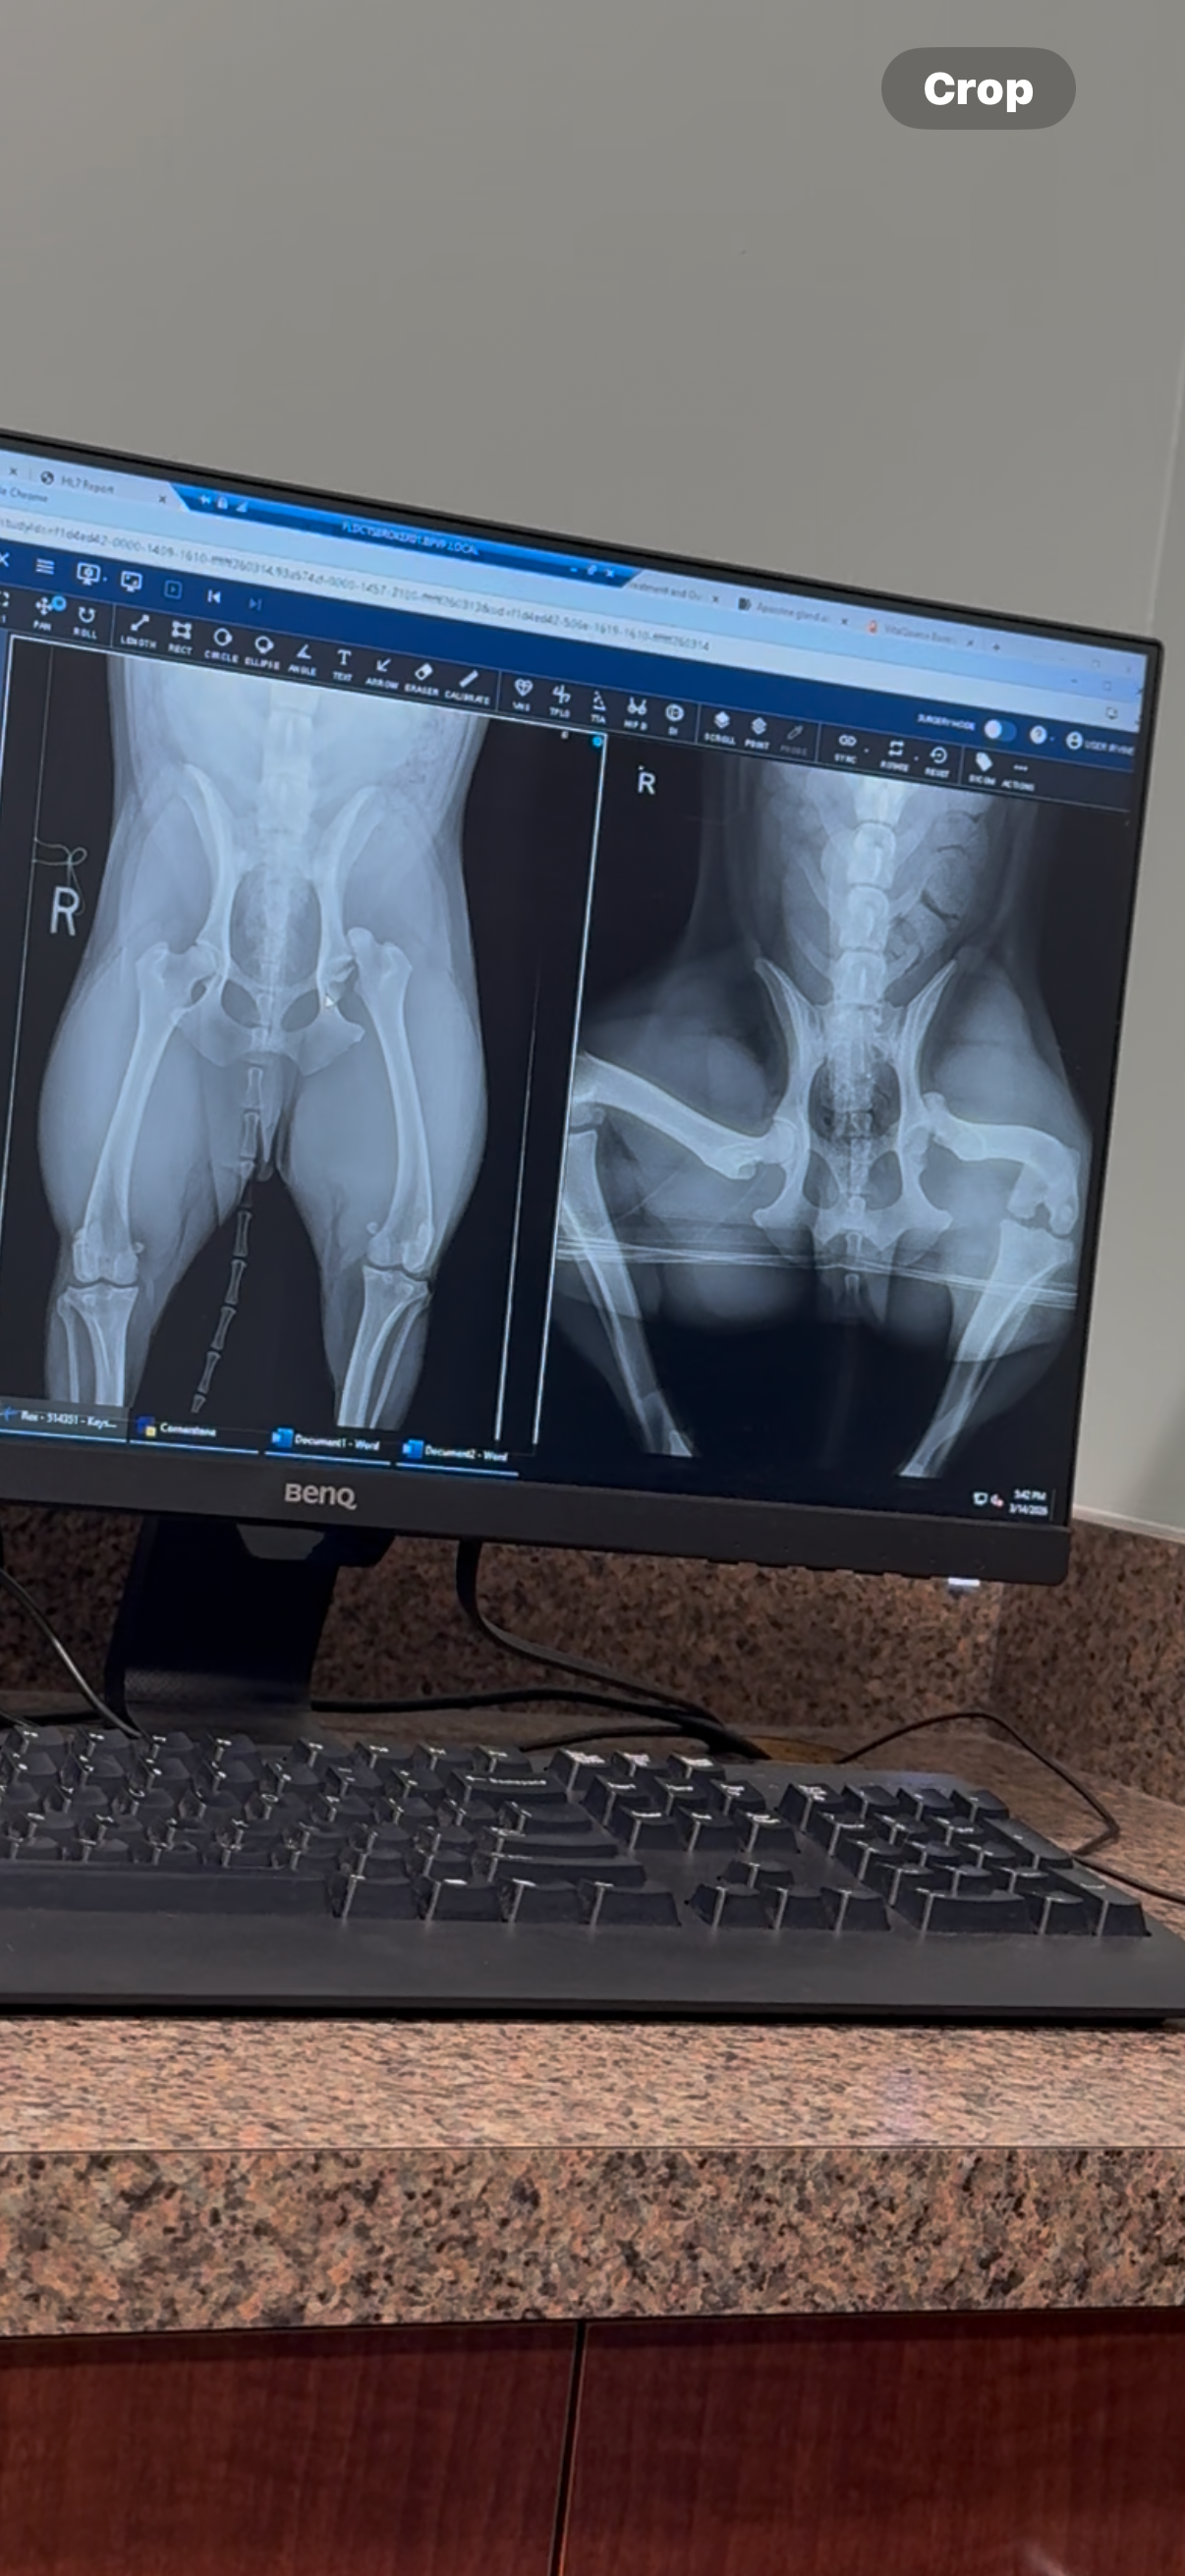

My sweet dog Rex was hit by a car after getting loose while on a walk with a ROVER dog walker near PCH and Myrtle. In a matter of seconds, our lives changed. Rex was struck by a vehicle and suffered a devastating injury to his hip.

Right now Rex is in severe pain and cannot walk normally. After veterinary evaluations, we’ve been told he will likely need a Femoral Head Ostectomy (FHO) surgery or a full hip replacement to give him a chance to walk and run again. In the worst case scenario, if his hip cannot be repaired, amputation may be the only option to relieve his pain and save his life.